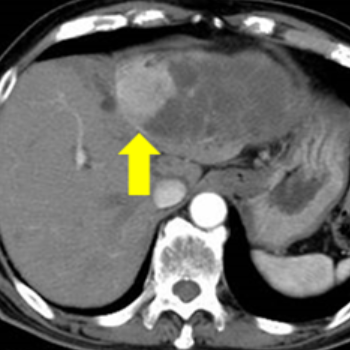

7. 간암의 초기증상 및 증상

간암의 경우 알려진 초기증상은 거의 없지만, 드물게 담관 주위에 암이 생기면 초기 무렵부터 황달이 보일 수 있습니다.

암이 간 내에서 어느 정도 진행하여 커지게 되면, 발열과 복수, 혈관의 팽창 등의 증상이 발생합니다. 또한 담관이 막히면서 황달이 보이는 특징이 있으며, 이런 증상이 나타나면 치료를 하더라도 생존율은 매우 적습니다.